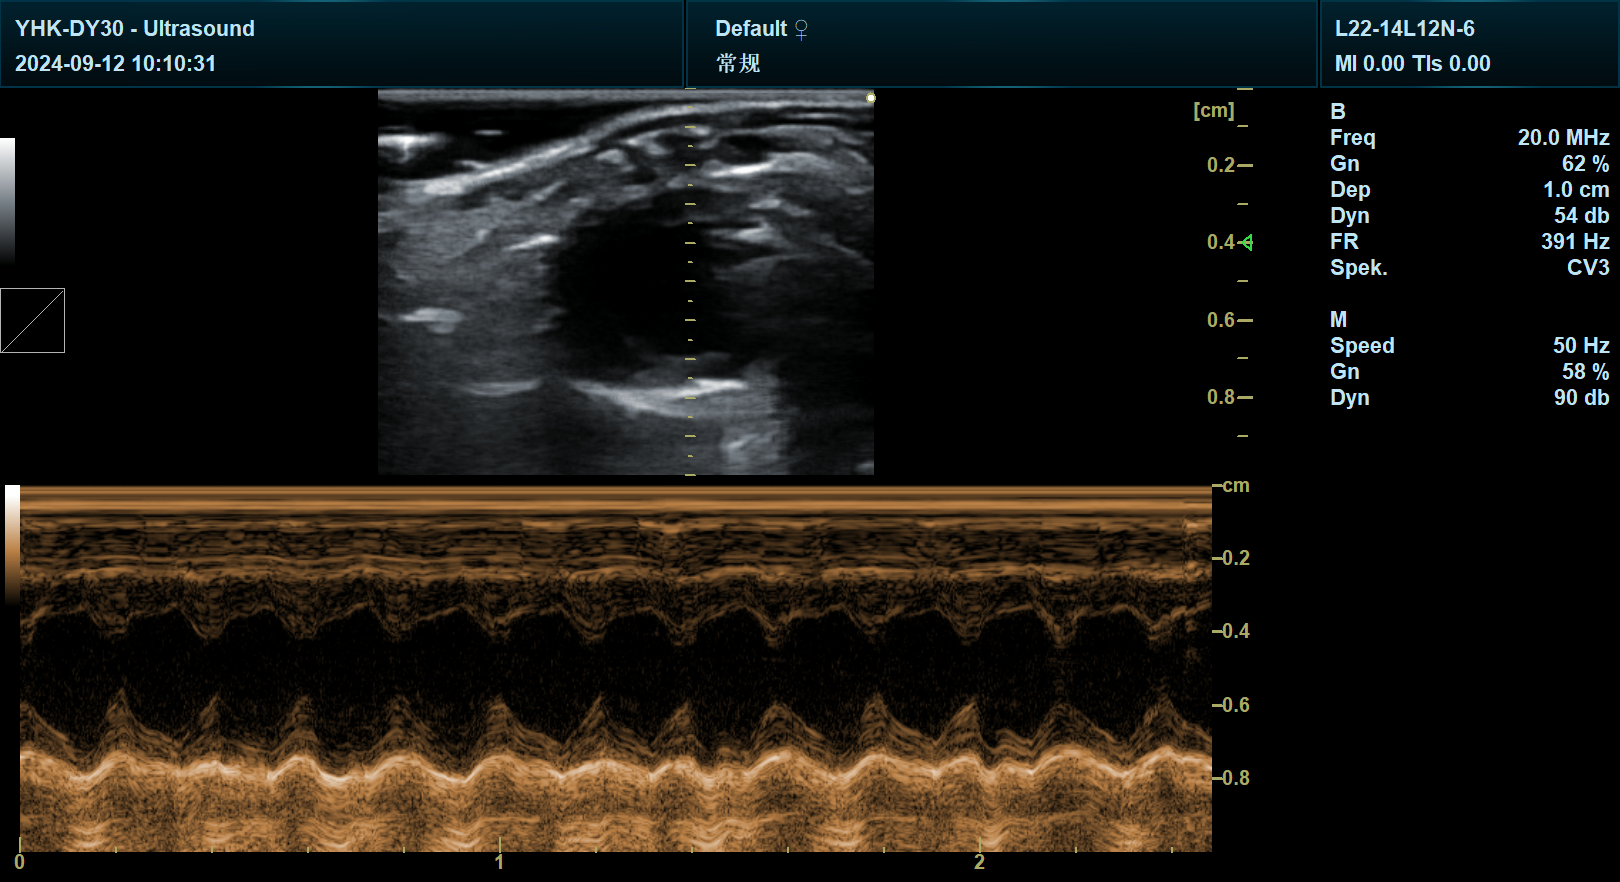

宜慧康科研彩超搭载256阵元电子线阵探头,工作频率覆盖7-15MHz,可实现50μm级空间分辨率,远超常规超声设备。在大小鼠心脏研究中,其23MHz超高频探头可清晰显示心肌纤维走向、瓣膜运动轨迹及微小血栓(如2mm级冠状动脉栓塞),为心肌病、先天性心脏病等模型提供关键形态学证据。例如,在心肌肥厚模型中,通过M型超声模块追踪室壁运动轨迹,结合左室功能分析软件,可自动化计算射血分数(EF值)与缩短分数(FS值),误差率低于3%。